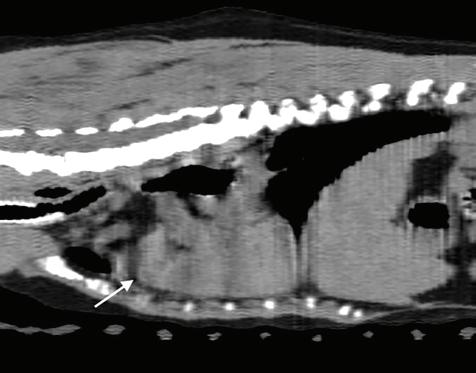

Se realizó una angio-TC de la cavidad torácica para caracterizar la masa mediastínica craneoventral. El estudio se realizó bajo anestesia general y con la paciente en decúbito esternal. Se realizaron series precontraste y post-contraste, inmediatamente y a los 3 minutos tras la administración de un contraste iodado hidrosoluble no iónico (iopromida 300 mg I/ml a una dosis de 600 mg I/kg intravenoso, administrado de forma manual) con cortes de 3 mm de grosor e intervalo 1,5 mm con algoritmo estándar (tejido blando) y pulmón. El estudio de TC se evaluó en ventana de tejido blando, hueso y pulmón, visualizándose en el área craneal al atrio derecho una estructura redon-

deada y bien definida (22UH) de medidas aproximadas 1,95 cm DV x 1,87 CrCd x 2,5 cm LL (Figs. 4 y 5). Tras la administración de contraste, esta estructura se llenó rápidamente de contraste de forma homogénea,

Figura 4. Imágenes de Tomografía Computarizada. Reconstruidas en plano sagital, simples (A) e inmediatamente tras la administración del contraste (B), en plano transversal, simples (C).

observándose una comunicación con el atrio derecho, midiendo el área de la comunicación 1,43 cm. El diagnóstico presuntivo fue de un aneurisma de la aurícula derecha.